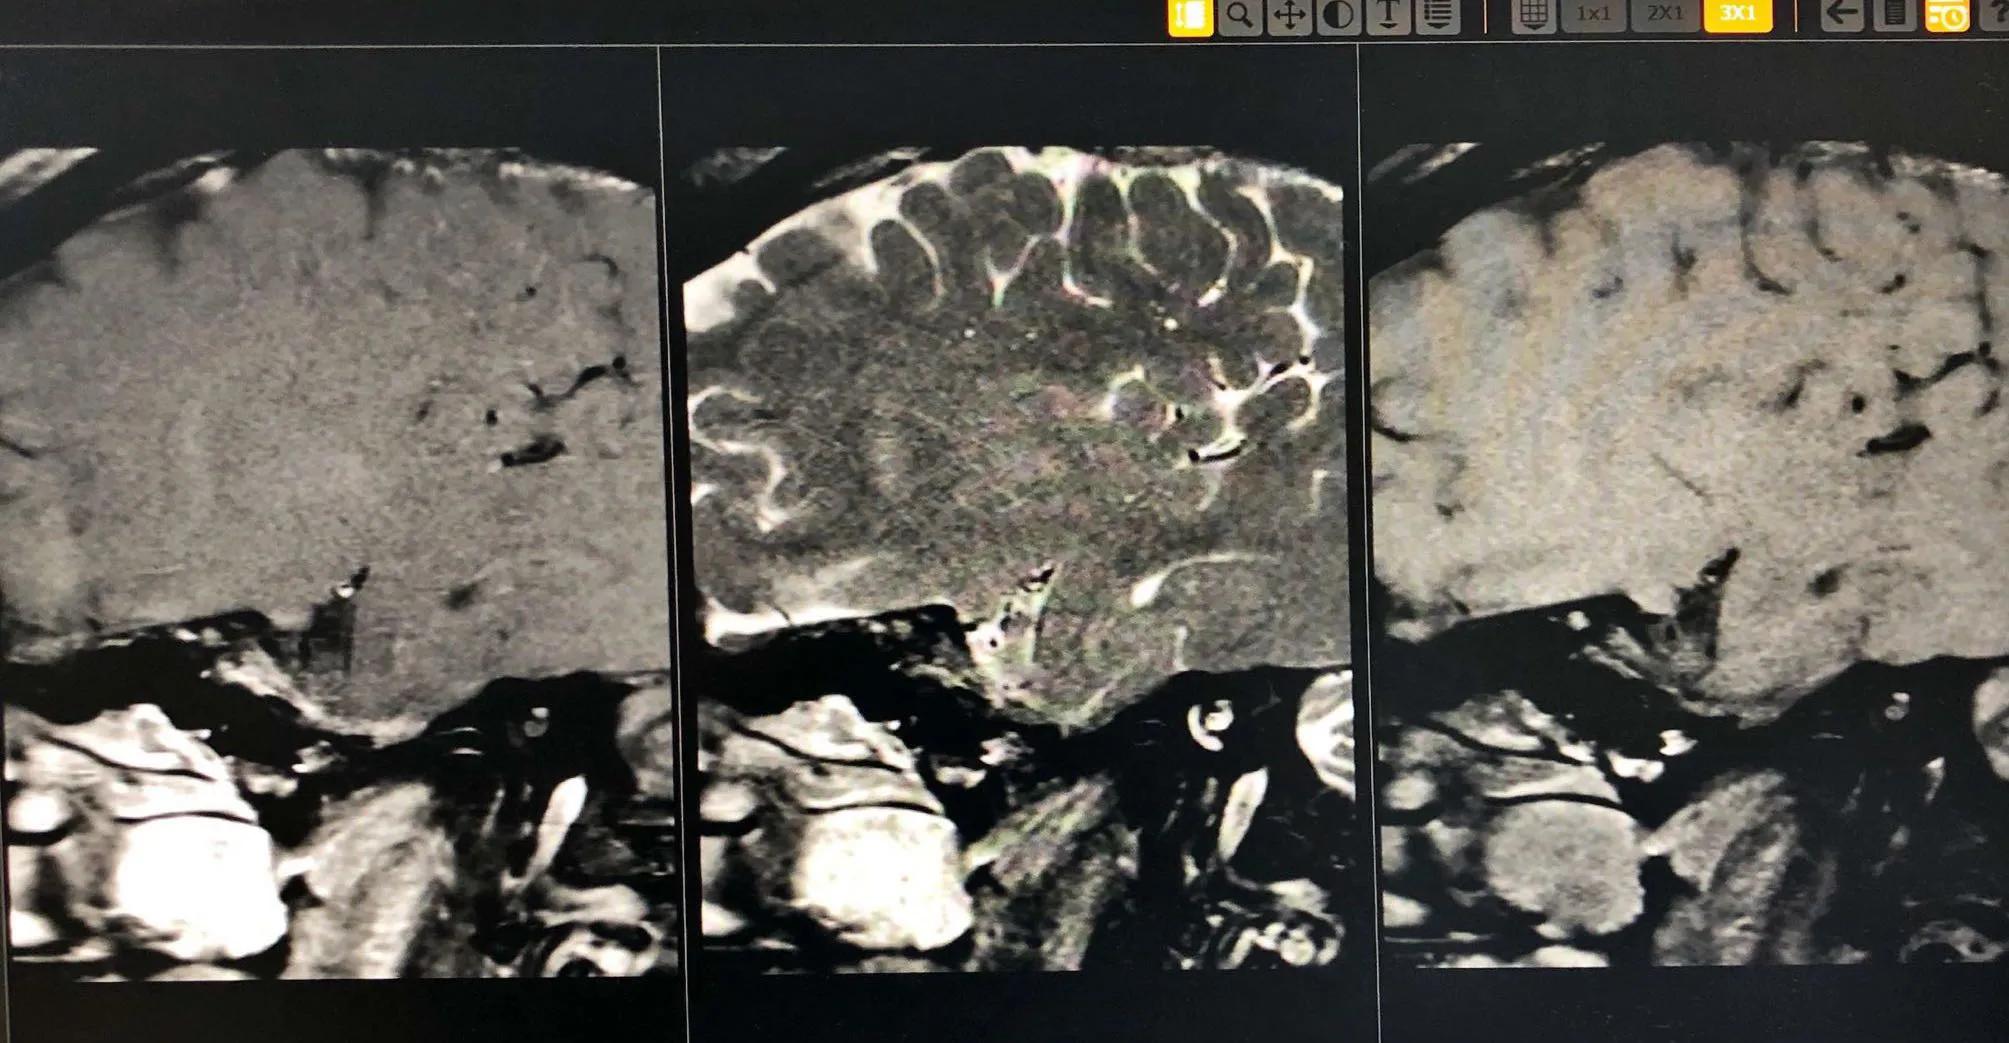

病例2.男,28岁,以“言语不清、右侧肢体无力4天”为主诉入院。2、既往史:否认“高血压、糖尿病、冠心病”病史抽烟2包/天·10年,喝酒;4天前喝酒半斤后患者出现言语不清、右侧肢体麻木无力,不伴有头痛呕吐,无听力下降、复视、饮水呛咳、吞咽困难及意识障碍,无大小便*禁失**,症状持续不缓解,就诊于河南省第三人民医院,查头MRI提示(河南省直第三人民医院 2020.08.20)示:1.左侧基底节区、额顶叶脑梗塞(急性期),2.头颅动脉血管硬化性改变,椎-基底动脉迂曲,3.双侧大脑中动脉及左侧大脑前、后动脉局限狭窄,4.左侧大脑中动脉分支稀疏,诊断为“急性脑梗死、脑动脉狭窄、烟雾病?”,治疗(具体不详)后症状有减轻,为求进一步明确病因诊治来我院,以“脑梗塞”收入我科。查体:BP140/105mmHg,神清、不完全运动行失语、中枢性面舌肢瘫、右上下肢肌力 Ⅳ级,粗测无明显感觉,右侧巴氏征(±)NIHSS评分4分。I、 左侧大脑中动脉斑块分析:1.左侧大脑中动脉斑块分析M1段局部管腔 中度 狭窄,并斑块形成,考虑不稳定斑块;

2.PWI:左侧侧脑室旁达峰时间(TTP)、平均通过时间(MTT)稍延长 ;造影情况如下:

病例3:男,19岁,以“发作性右侧面部、右侧肢体麻木2天,再发加重4小时”为主诉入院。2天前熬夜后(已连续熬夜2周后休息1天)突然出现右侧面部、右侧肢体麻木,无头痛头晕、呕吐、言语不清,无视物重影、饮水呛咳、吞咽困难,无肢体无力及意识障碍等,持续约15分钟后完全缓解,未在意。4小时前患者再次出现右侧面部、右侧肢体麻木,伴言语不清、右侧肢体无力,右上肢可上抬,右下肢行走需搀扶,症状持续约30分钟完全缓解,后上述症状又反复发作3次,为求进一步治疗,急来我院,急查头CT:未见出血,急查头磁共振提示“颅内多发脑梗死”,急诊以“脑梗死”收入我科。3.既往史:吸烟史6年余,平均6根/天;否认“冠心病、高血压病、糖尿病”史;神经系统:神清,语利,智能可,双侧鼻唇沟对称,伸舌居中,四肢肌张力正常,肌力Ⅴ级,四肢腱反射(++)。双侧痛觉对称存在,双侧指鼻试验、跟膝胫试验稳准,双侧巴氏征(-),脑膜刺激征阴性,NIHSS评分:0分;磁共振(2017.07.01我院):1.左侧额顶叶、基底节区、侧脑室旁异常信号,考虑:急性期脑梗塞(TSI:貌似TIA的脑梗塞);颅脑MRA左侧大脑中动脉M1段纤细、远端血流显影浅淡……

入院后完善相关检查:颅脑CTA:1.左侧大脑中动脉M1段局部中度狭窄;2.左侧后交通动脉开放;高分辨磁共振成像示左侧大脑中动脉M2段重度狭窄伴动脉粥样硬化斑块形成(考虑不稳定斑块)